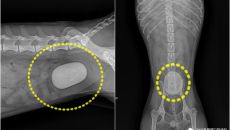

"AI로 만든 줄"…혈뇨로 병원 찾은 푸들, 방광 가득 채운 거대 결석

(서울=뉴스1) 한송아 기자 = 혈뇨 증상으로 병원을 찾은 소형견의 방광에서 방광을 거의 가득 채운 거대 결석이 발견돼 수술로- 22시간전

- 뉴스1